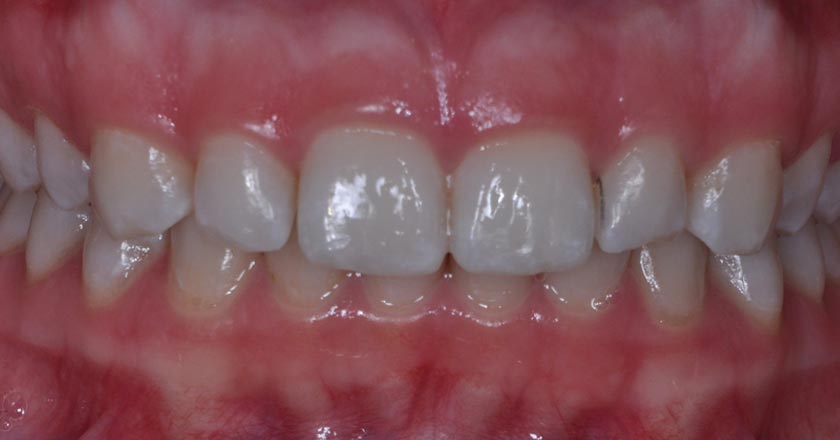

Implant - Before And After